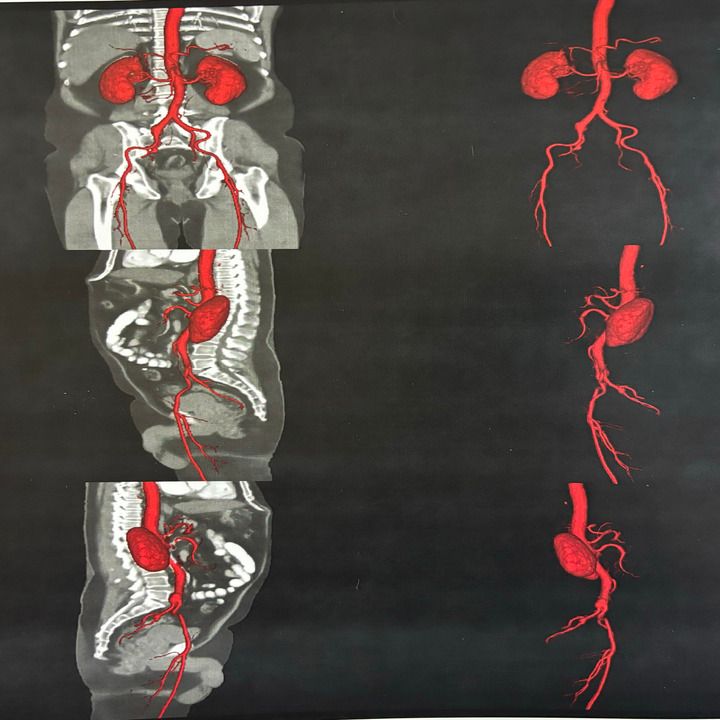

• Cirugía arterial

• Cirugía endovascular

• Diagnóstico vascular no invasivo